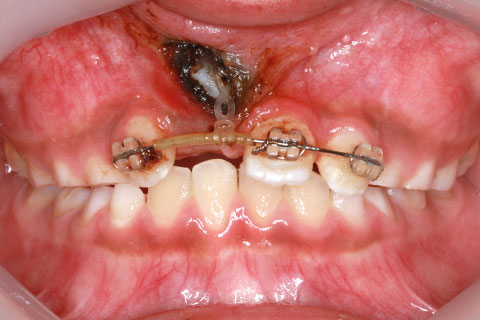

子供の乳歯が抜けて、かなりの時間が経つのに永久歯が生えてこないと心配して来院される親御様は多くいらっしゃいます。この場合、レントゲンにて確認すると大体の場合、もうしばらく待っていれば生えてくるであろうと予測がつきます。しかし、稀に歯の位置異常により、埋まったままの状態で生えてこないことがあります。この場合、待っていても生えてきませんので、矯正力により歯を引っ張り出す必要があります。これを矯正学では開窓・牽引術と呼び、歯肉を切開して、歯の表面を露出させ、そこに矯正器具を付けて、良好な位置まで引っ張り出すという治療法です。

開窓・牽引の症例